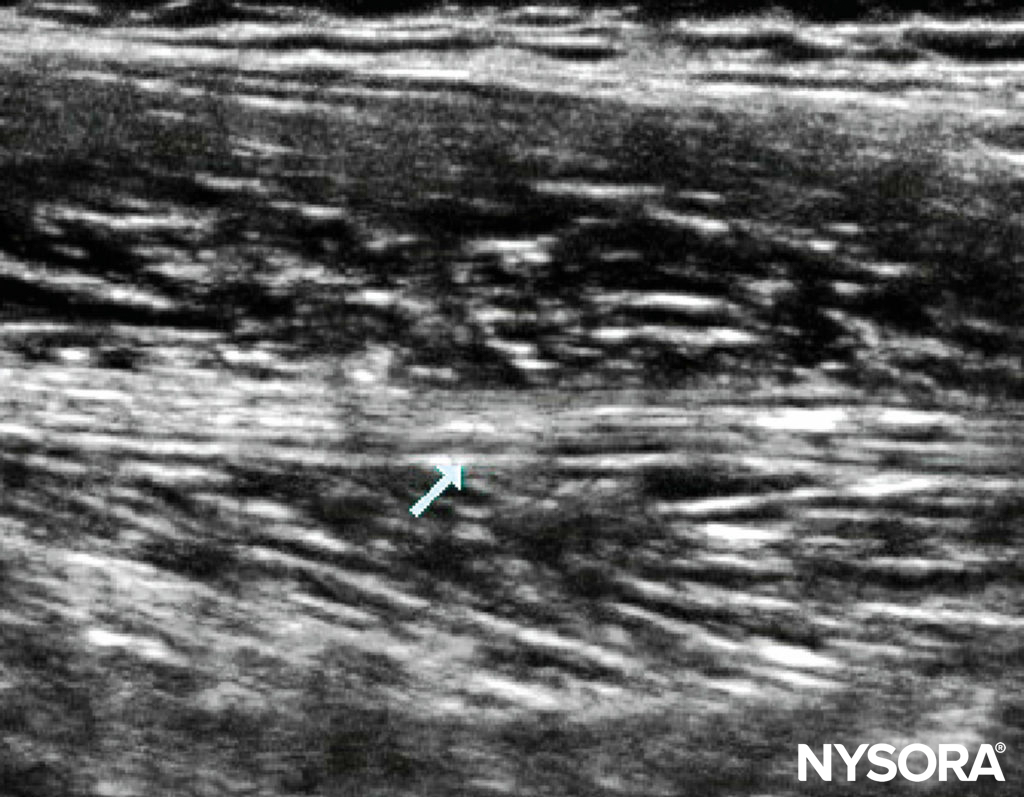

Ultrasound-Guided Technique A linear probe suffices in all but the largest adolescent. Applying probe pressure improves the US image, as this brings the sciatic nerve closer to the probe (Figure 6). Visualizing the nerve may be difficult in arthrogrypotic children, in whom it may be obscured by fibrosis. Where there is difficulty identifying the nerve, a longitudinal scan from medial to lateral and back may be attempted, looking for a band of hyperechogenicity (Figure 7). Once the sciatic nerve identified, rotate the probe back into the transverse plane. Alternatively, track down distally to the popliteal fossa, and identify the nerve before retracing your steps. With US, it is often possible to see the posterior cutaneous branch of the thigh, medial and superficial to the sciatic nerve, and it is important to ensure the local anesthetic covers it. An in-plane technique is advisable for single injections, whereas an out-of-plane technique is often better for catheter placement. When placing catheters, first inject one-third of the available local anesthetic by the lateral aspect of the nerve; the remaining two-thirds is used medially to make space for the catheter. This technique ensures the nerve is surrounded.

FIGURE 6. Probe position and sonoanatomy at the subgluteal level

FIGURE 7. Longitudinal scan of the thigh highlighting the sciatic nerve in a 6-year-old.